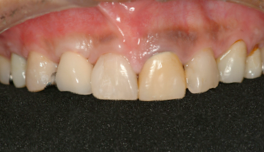

右の前歯が一本ありません。

最初の仮歯の状態です。

症例2

前歯の場合笑った時の歯の

見え方、歯茎の見え方も注意してインプラントの位置を考え

なければなりません。

他の残っているご自分の歯に

形を合わせないと審美的に

満足はえられません。